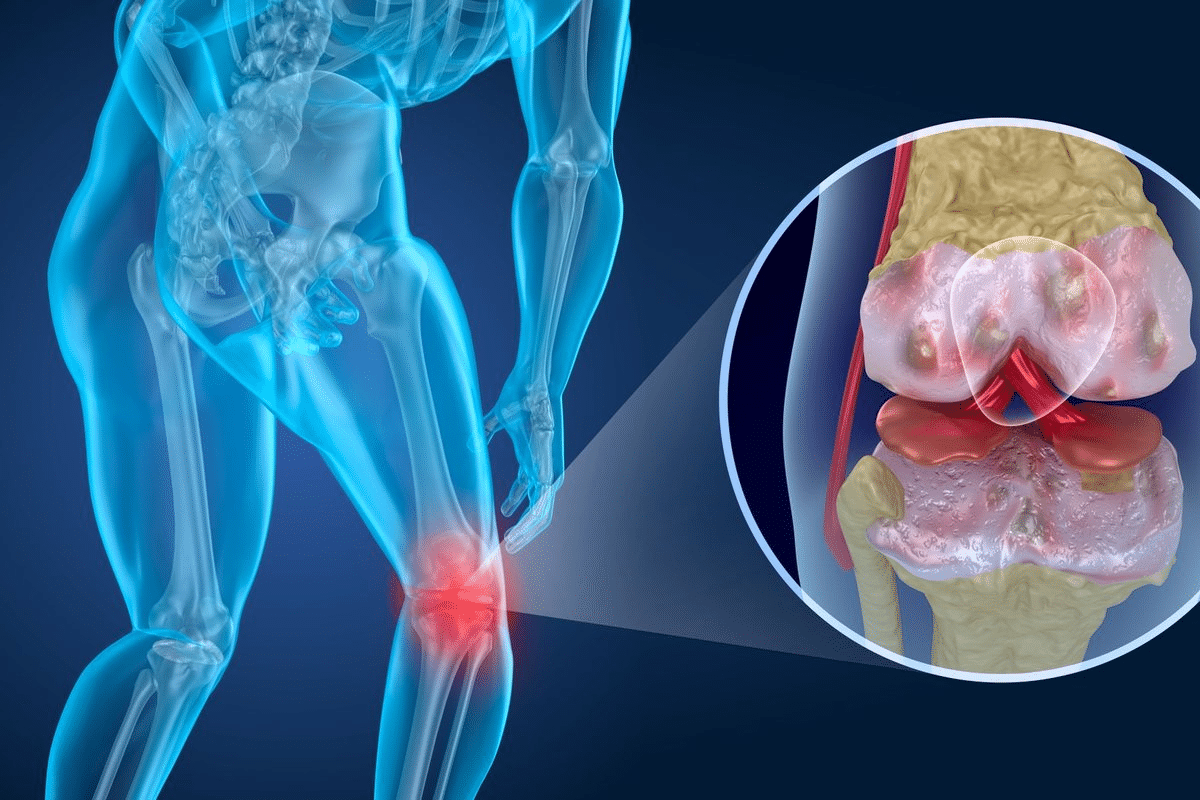

It’s important to know about the different types of inflammatory joint diseases. These conditions can really hurt your quality of life. They cause pain, stiffness, and make it hard to move.

Rheumatoid arthritis (RA) is a chronic condition that mainly affects the joints. It causes inflammation, pain, and can damage the joints over time. If one hand is affected, the other hand usually is too.

Osteoarthritis (OA) is the most common arthritis. It’s often called “wear and tear” arthritis. It happens when cartilage in joints breaks down, causing pain. Unlike RA, OA is not an autoimmune disease but a degenerative condition.

Inflammatory joint disease is when joints get inflamed. This leads to pain, stiffness, and less mobility. Conditions like rheumatoid arthritis and osteoarthritis fall under this category.